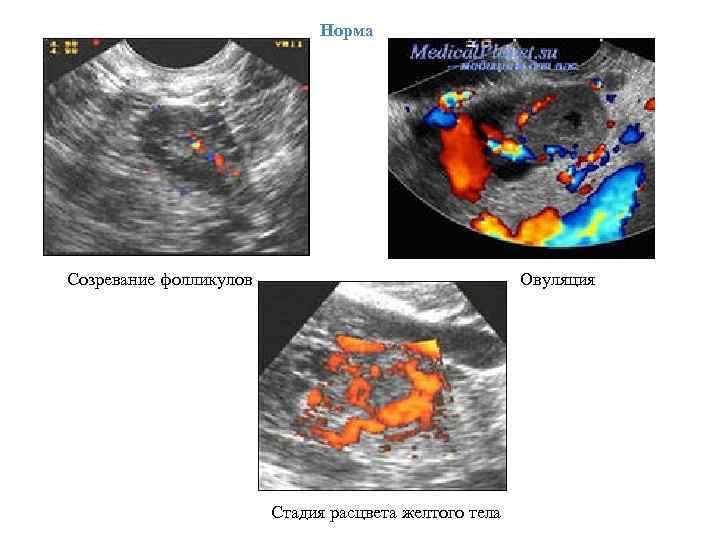

1) Эхография Норма ЛНФ Размеры фолликула увеличиваются за 4 дня до овуляции от 19 мм до 27 мм Пик ЛГ Исчезновение фолликула на эхограмме Размеры фолликула увеличиваются за 4 дня до овуляции от 19 мм до 27 мм Пик ЛГ Сохранение фолликула Постепенное уменьшение его размеров с одновременным утолщением стенки Увеличение его размеров

Допплерографическое исследование Норма • Увеличение перфузии желтого тела ЛНФ • Снижение перфузии желтого тела

Норма Созревание фолликулов Овуляция Стадия расцвета желтого тела